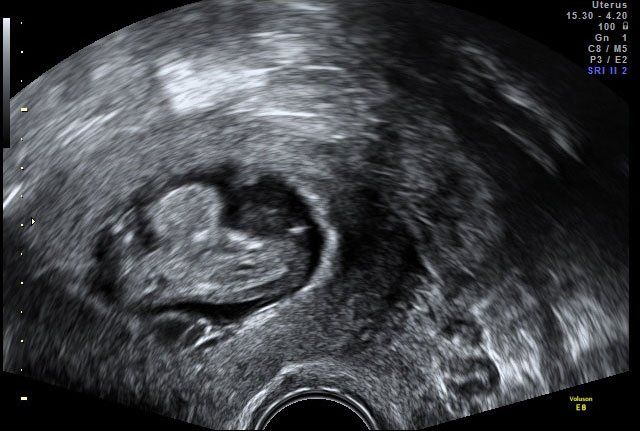

Παθολογικά Περιστατικά

Δισχιδής Ράχη - Spina Bifida

Κυφοσκολίωση εμβρύου

Τρισωμία 21 σε δίδυμη κύηση

Ύδρωπας εμβρύου

Εξόμφαλος

Παθολογικό Περιστατικό με σύνδρομο Down